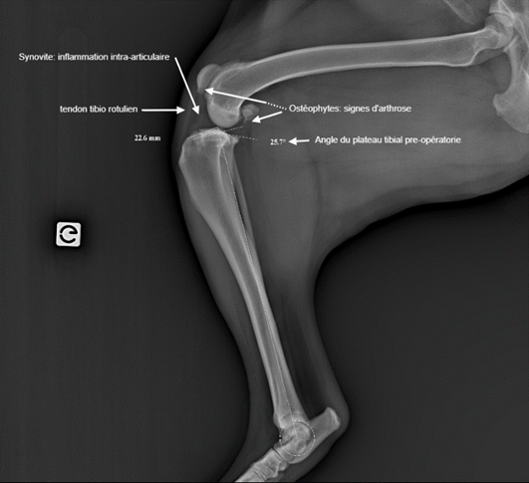

Quand on palpe le genou celui-ci est fréquemment gonflé, signe de synovite, donc de présence de liquide inflammatoire dans l’articulation du genou.

Une radiographie est ensuite conseillée afin de visualiser l’articulation du genou et de juger de son inflammation et de son instabilité.

Le gold standard chez le chien passe par une intervention chirurgicale, appelée TPLO (nivellement du plateau tibial), qui modifie la conformation du genou afin de neutraliser la poussée tibiale crâniale. L’orientation des forces qui s’exercent sur le genou sont modifiées avec la chirurgie et permettent une stabilisation dynamique du genou. Cette intervention passe par une ostéotomie, stabilisée à l’aide d’une plaque et de vis.